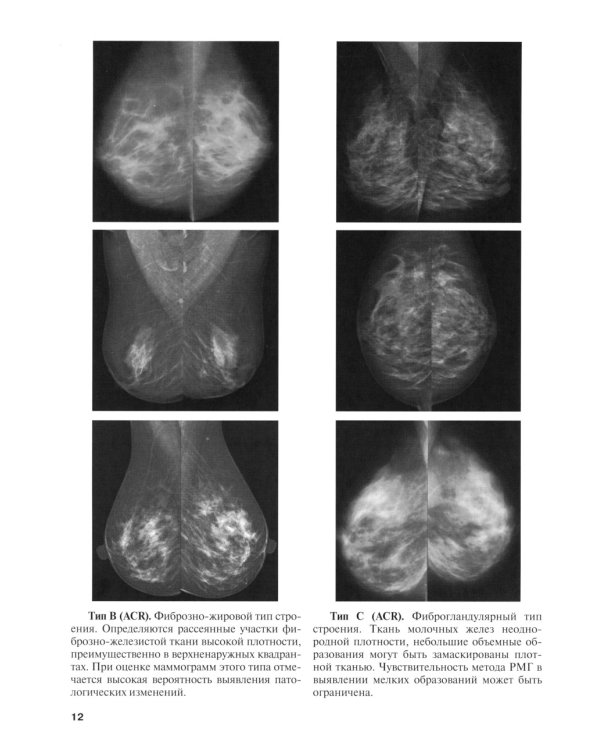

В руководстве представлен адаптированный к повседневной клинической работе перечень понятий и терминов, используемых в современной описательной системе BI-RADS. Подробное описание категорий, присваиваемых в результате комплексного лучевого исследования, упростит внедрение классификации в рутинную практику специалистов, занимающихся оценкой состояния молочных желез. Богато иллюстрированное издание, с наглядными клиническими примерами может использоваться как для первичного обучения в рамках клинической ординатуры, так и в процессе повышения квалификации практикующих врачей. Данное руководство предназначено для практикующих врачей лучевой диагностики, рентгенологов, ультразвуковых специалистов, врачей магнитно-резонансной томографии, маммологов, онкологов, врачей общей практики.| Издательство | Элби |